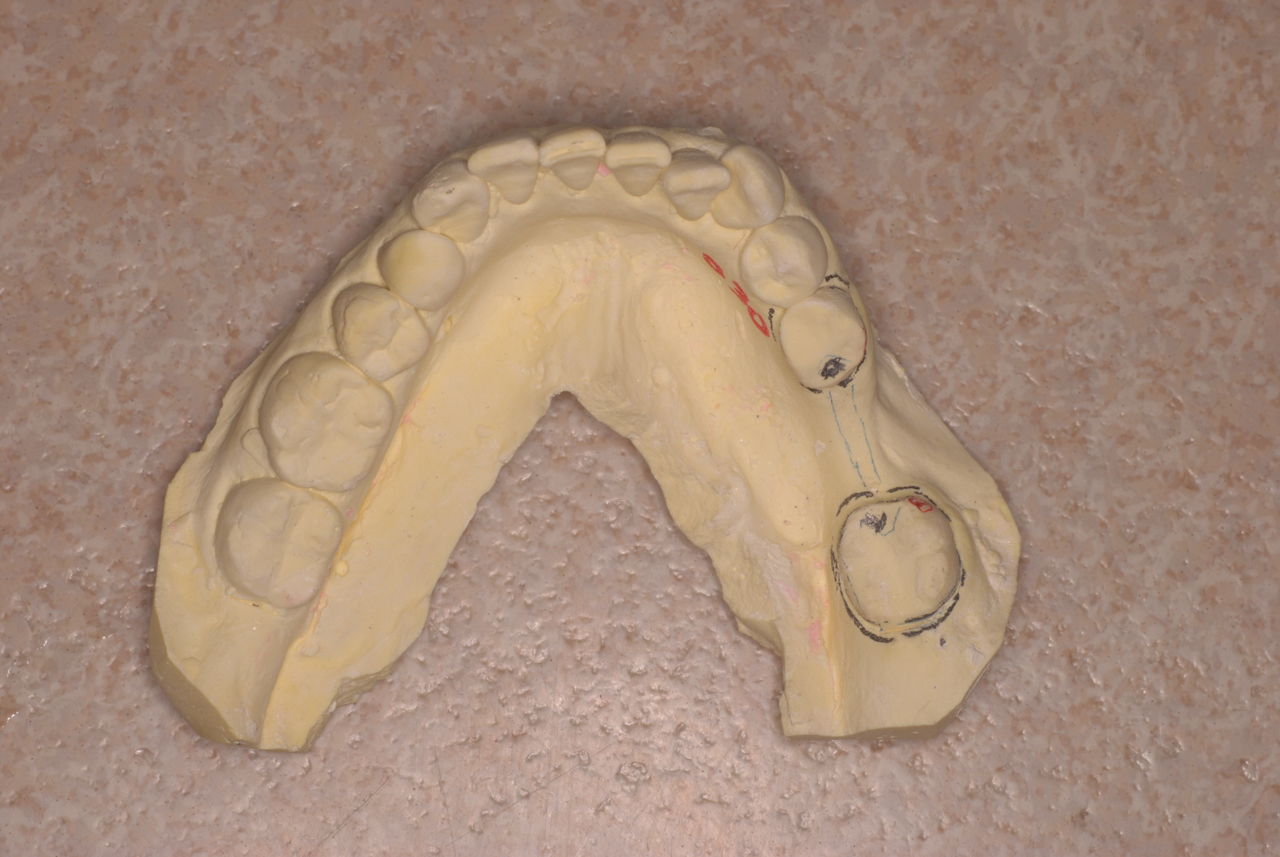

歯をいじられ体も心もボロボロになった患者さんからの手紙です。マスコミや権威などがいかにいい加減かわかります。歯は触らないほうがよろしいのです。

昭和60年代ぐらいから、私は歯を触るとか矯正するとかマウスピースをして顎の関節の症状を治癒するなどというような処置はしなくなってきました。

そもそも歯を触り何らかの金属やセラミックを入れる行為そのものが医学的には傷害処置ですから、なるべく避けるべき物なのです。